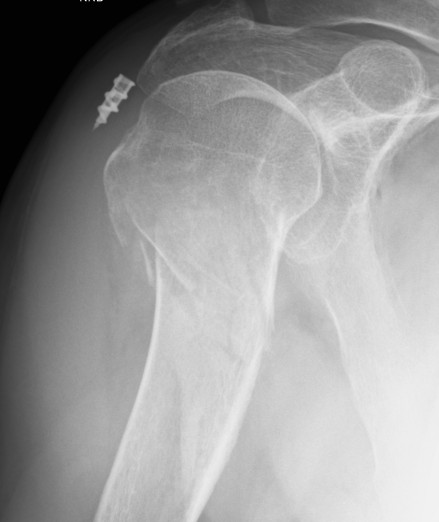

Retear

Increased risk with larger tear size and patient age

- 1000 arthroscopic RCR with ultrasound at 6 months

- retear in 27% of full thickness tears

- increased risk as tear size increased

- increased risk with older patients

- 1600 arthroscopic RCR

- retear rate 7% with cuff tears < 2 cm2

- retear rate 44% with tears > 8 cm2

Increased risk with fatty degeneration